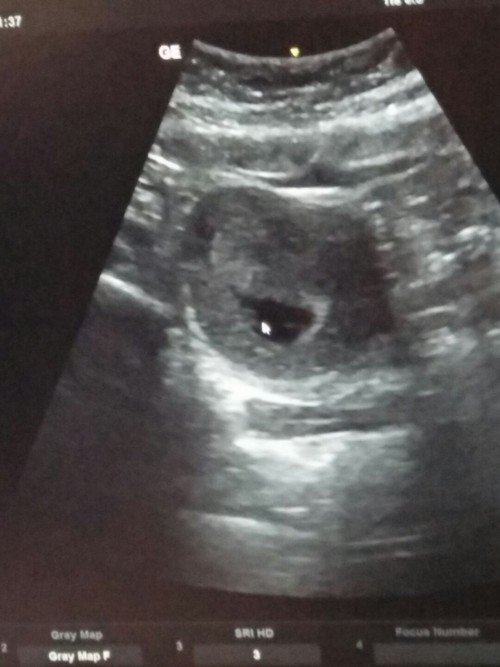

อายุครรภ์ 7 สัปดาห์ไปซาวน์ดูน้องยังไม่เจอเลยค่ะ แบบนี้ปกติอยู่ไหมค่ะ แอบกังวลนิดค่ะ ขออนุญาติสอบถาม

ต้องดูว่าคุณหมอซาวน์แบบไหนคะ ทางนี้7สัปดาห์ 2วัน เจอน้องคะ แต่ซาวน์ผ่านช่องคลอดนะค่ะ ได้ยินเสียงหัวใจด้วย ขัวร์กว่าคะ ผ่านหน้าท้องอ่จจะไม่เจอ

ไม่เกิน 10 week เดี๋ยวก็เจอค่ะ บ้านนี้เจอตอน 6 week ทั้งตัวน้องและเสียงหัวใจ

เราเจอตอน9สัปดาห์ค่ะ ยังมองแทบไม่ออกเลย หมอต้องเอาเม้าชี้ให้ดู

บ้านนี้ตอน 7wเจอตัวน้องเเล้วนะคะ เจอหัวใจเต้นเเล้วด้วยค่ะ

ของเราตอน8วีคคะ ได้ยินทั้งเสียงหัวใจ ทั้งเห็นหัวใจเต้น

ตอน6w เจอตัวอ่อนค่ะ เล็กมากๆ ซาวด์ผ่านช่องคลอด

ตอน7สัปดาห์ ของเราเห็นเป็นหัวใจเต้นค่ะ

น้องอาจจะยังตัวเล็กอยู่ค่ะ

เราเจอตัวน้องตอน 8w ค่ะ